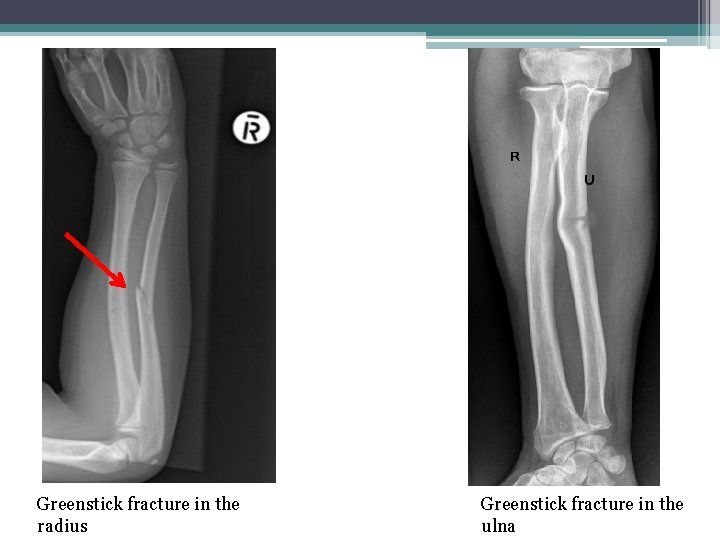

• 5 -Greenstick Fracture: : Incomplete fracture that usually occurs in children (the bone partly fractures on one side, but does not break completely because the rest of the bone can bend).

Greenstick fracture in the radius Greenstick fracture in the ulna